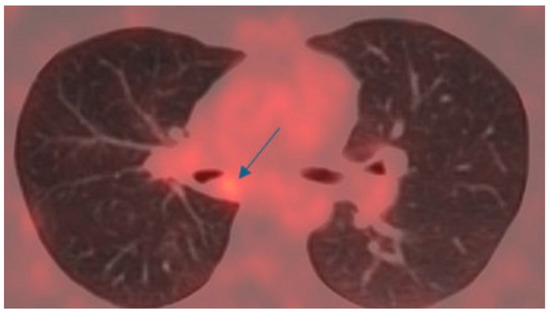

4.2. Case 2